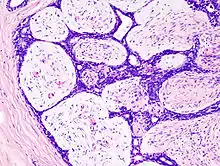

Microscopic

Fibroadenoma of the breast is a benign tumor composed of a biplastic proliferation of both stromal and epithelial components.[14][15] This biplasia can be arranged in two growth patterns: pericanalicular (stromal proliferation around epithelial structures) and intracanalicular (stromal proliferation compressing the epithelial structures into slit-like spaces).

These tumors characteristically display hypovascular stroma compared to malignant neoplasms.[16][17][11] Furthermore, the epithelial proliferation appears in a single terminal ductal unit and describes duct-like spaces surrounded by a fibroblastic stroma. The basement membrane is intact.[18]

Histopathologic image of breast fibroadenoma showing proliferation of intralobular stroma compressing and distorting the epithelium. H&E stain.